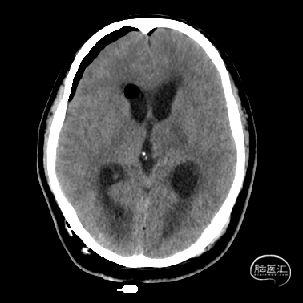

术后当天CT

1.完成手术目的,“一箭双雕”,既切除了海绵状血管瘤,又缓解了脑积水;

5.术后72小时复查磁共振提示海绵状血管瘤全切。